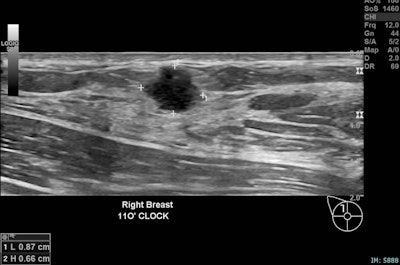

Right breast, 11 o’clock position, same patient. An 11 mm irregular hypoechoic solid lesion with microlobulated margins, ductal extension, adjacent fat plane distortion, and internal vascularity on Doppler. This corresponds to the palpable abnormality. Biopsy confirmed invasive ductal carcinoma, Grade 2, ER positive, PR positive, HER2 positive, concordant with imaging findings.